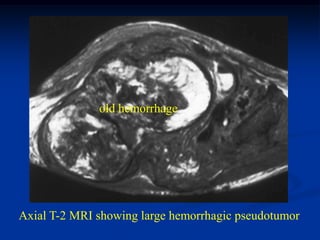

old hemorrhage

Axial T-2 MRI showing large hemorrhagic pseudotumor